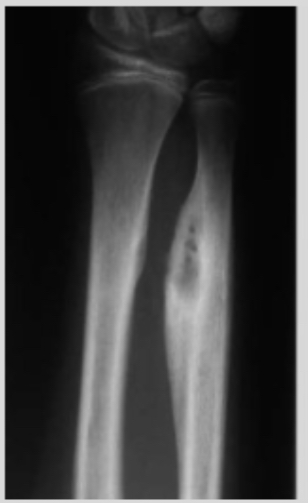

This study examined professional bareback rodeo riders (without a saddle), showing extreme bone hypertrophy in the ulna. The hypertrophy results from direct trauma and impact with the hip bone. For perspective, some individuals had up to a 92% increase in bone diameter and a 268% increase in cross-sectional area, which is extremely unusual. The image in the study shows significant hypertrophy, though not the individual with nearly doubled bone diameter.

If anyone claims this hypertrophy is caused by muscle pull alone, that is incorrect. The main reason is direct trauma to the bone, supported by the following:

- Many other sports generate high torsional forces on the bone, but hypertrophy does not exceed 10% compared to rodeo riders, indicating torsion alone cannot explain the extreme growth. Direct trauma plays a key role.

- The hypertrophy occurs only in the area where the humerus contacts the hip bone, exactly at the point of contact and impact. This localized growth confirms direct pressure and trauma are the main causes.

- Hypertrophy was observed only in riders without a saddle, where the humerus presses directly against the hip. Saddles act as a barrier that reduces direct pressure and trauma, preventing bone growth.

- The large variation in hypertrophy between individuals is due to some using protective pads that reduce trauma, while others did not. This shows how protection affects trauma and the extent of hypertrophy.

- Significant hypertrophy is seen in bareback riders, but not in saddle riders, further supporting that direct trauma and impact are the main drivers of bone growth.